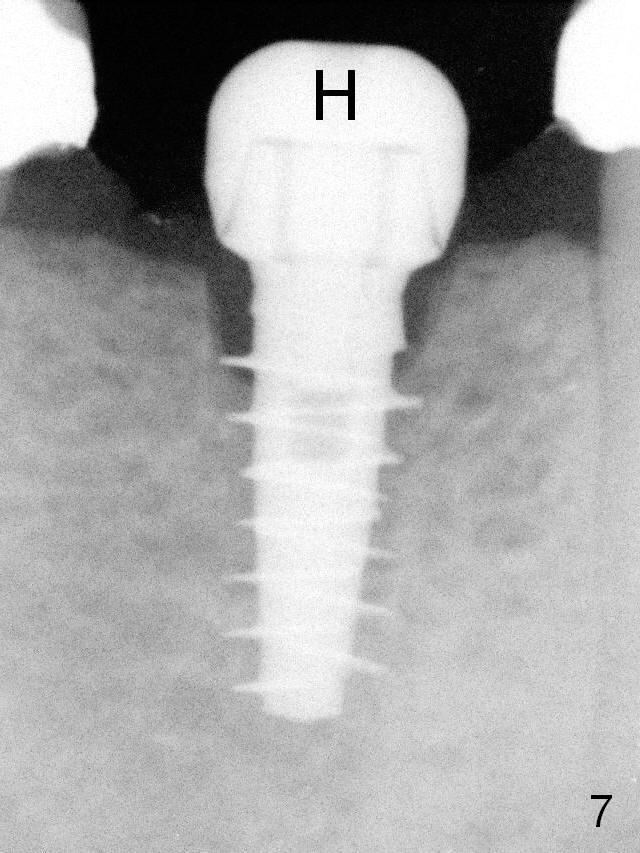

A 4.5x9(1) mm Magicore is placed with 35 Ncm (insertion torque) after 4.3 mm Magic Drill; a 4.5 mm healing abutment is inserted (Fig.7 H). An error occurs because of using 1 mm cuff of the Magicore. Ideally 3 or 4 mm cuff should have been used because of reduction in the ridge by ~ 3 mm (Fig.2). The result of the error is failure of placing the implant at the desirable depth (<9 mm). The coronal threads are exposed and have to be covered by bone graft (autogenous bone and allograft (.5-1.5 mm) (Fig.8 *), followed by collagen dressing.